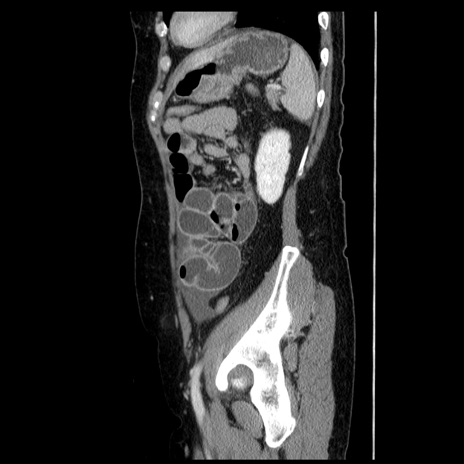

症例6(矢状断像)

【症例】50歳代女性

【主訴】下腹部痛

【現病歴】本日朝より下痢2回あり。 昼食を食べた後、嘔吐3回、下腹部痛認め、症状軽快せず、当院救急搬送。

【既往歴】卵巣癌術後(8年前に当院で卵巣摘出)

【身体所見】 意識清明、腹部:平坦、腸蠕動音→、やや硬、下腹部自発痛・圧痛あり、反跳痛あり、筋性防御なし。

【データ】WBC 16000、CRP 0.01